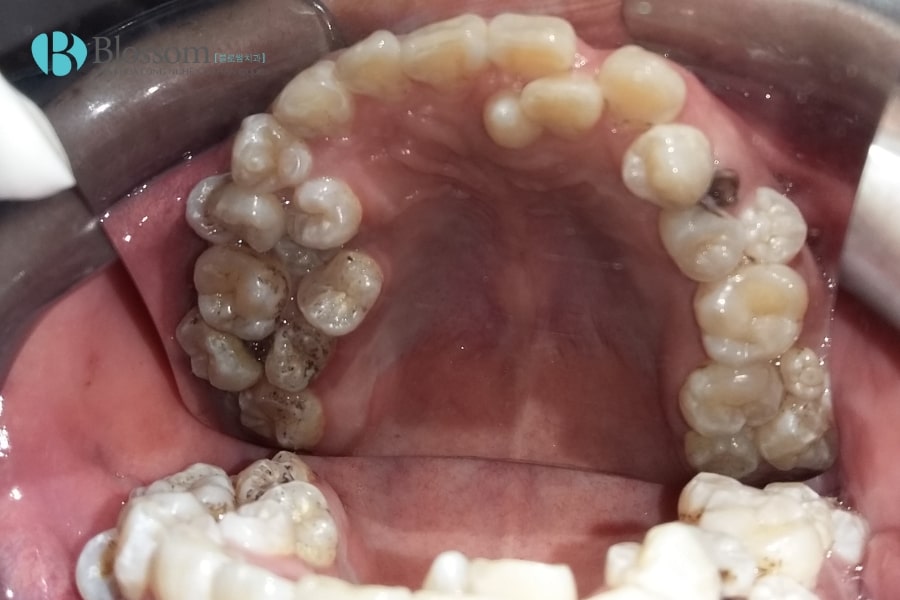

Mọc thừa răng (răng dư, răng kẹ, hyperdontia) là tình trạng có nhiều hơn số răng bình thường và vượt quá 20 răng sữa hoặc 32 răng vĩnh viễn. Răng thừa có thể mọc ở bất kỳ vị trí nào trên cung hàm, phổ biến nhất là vùng răng cửa hàm trên. Chúng thường nhỏ, dị dạng, mọc lệch hoặc ngầm, không có chức năng ăn nhai và có thể ảnh hưởng đến thẩm mỹ, sức khỏe răng miệng.

2.1. Mọc thừa răng ở hàm trên

Đây là vị trí thường gặp nhất. Răng thừa ở hàm trên có thể mọc ở phía sau răng cửa, giữa hai răng cửa hoặc lệch ra ngoài cung hàm. Một số trường hợp, răng thừa còn mọc ở vùng hàm ếch, gây khó khăn khi phát hiện và vệ sinh răng miệng.

2.4. Mọc thừa răng ngầm

Răng thừa mọc ngầm nằm ẩn trong xương hàm, không thể nhìn thấy bằng mắt thường mà chỉ phát hiện qua chụp X-quang. Nếu không điều trị, răng ngầm có thể gây áp lực lên răng bên cạnh, dẫn đến tiêu xương, u nang hoặc đau nhức kéo dài.